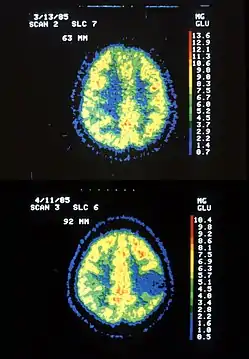

Астроцитома піддається діагностиці, видаляють її лише хірургічним шляхом. Для виявлення пухлини роблять комп'ютерну томографію (КТ) та магнітно-резонансну томографію (МРТ). При підозрі на пухлину обов'язково проводять біопсію. Для цього розкривають череп, потім забирають зразок тканини мозку, який вивчають під мікроскопом на наявність пухлинних клітин, і якщо вони виявлені, то видаляється якомога більша частина пухлини[3].